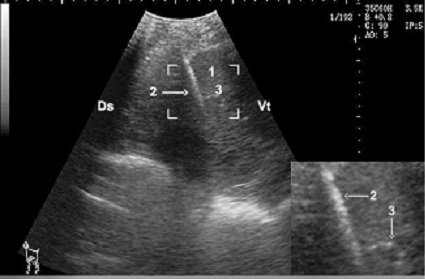

Hepatic biopsy in a doe, notice the needle is clearly visible as hyper-echoic structure (zoom area) within the hepatic parenchyma

1: Liver parenchyma; 2: Biopsy needle; 3: Portal vein; Ds: Dorsal; Vt: Ventral